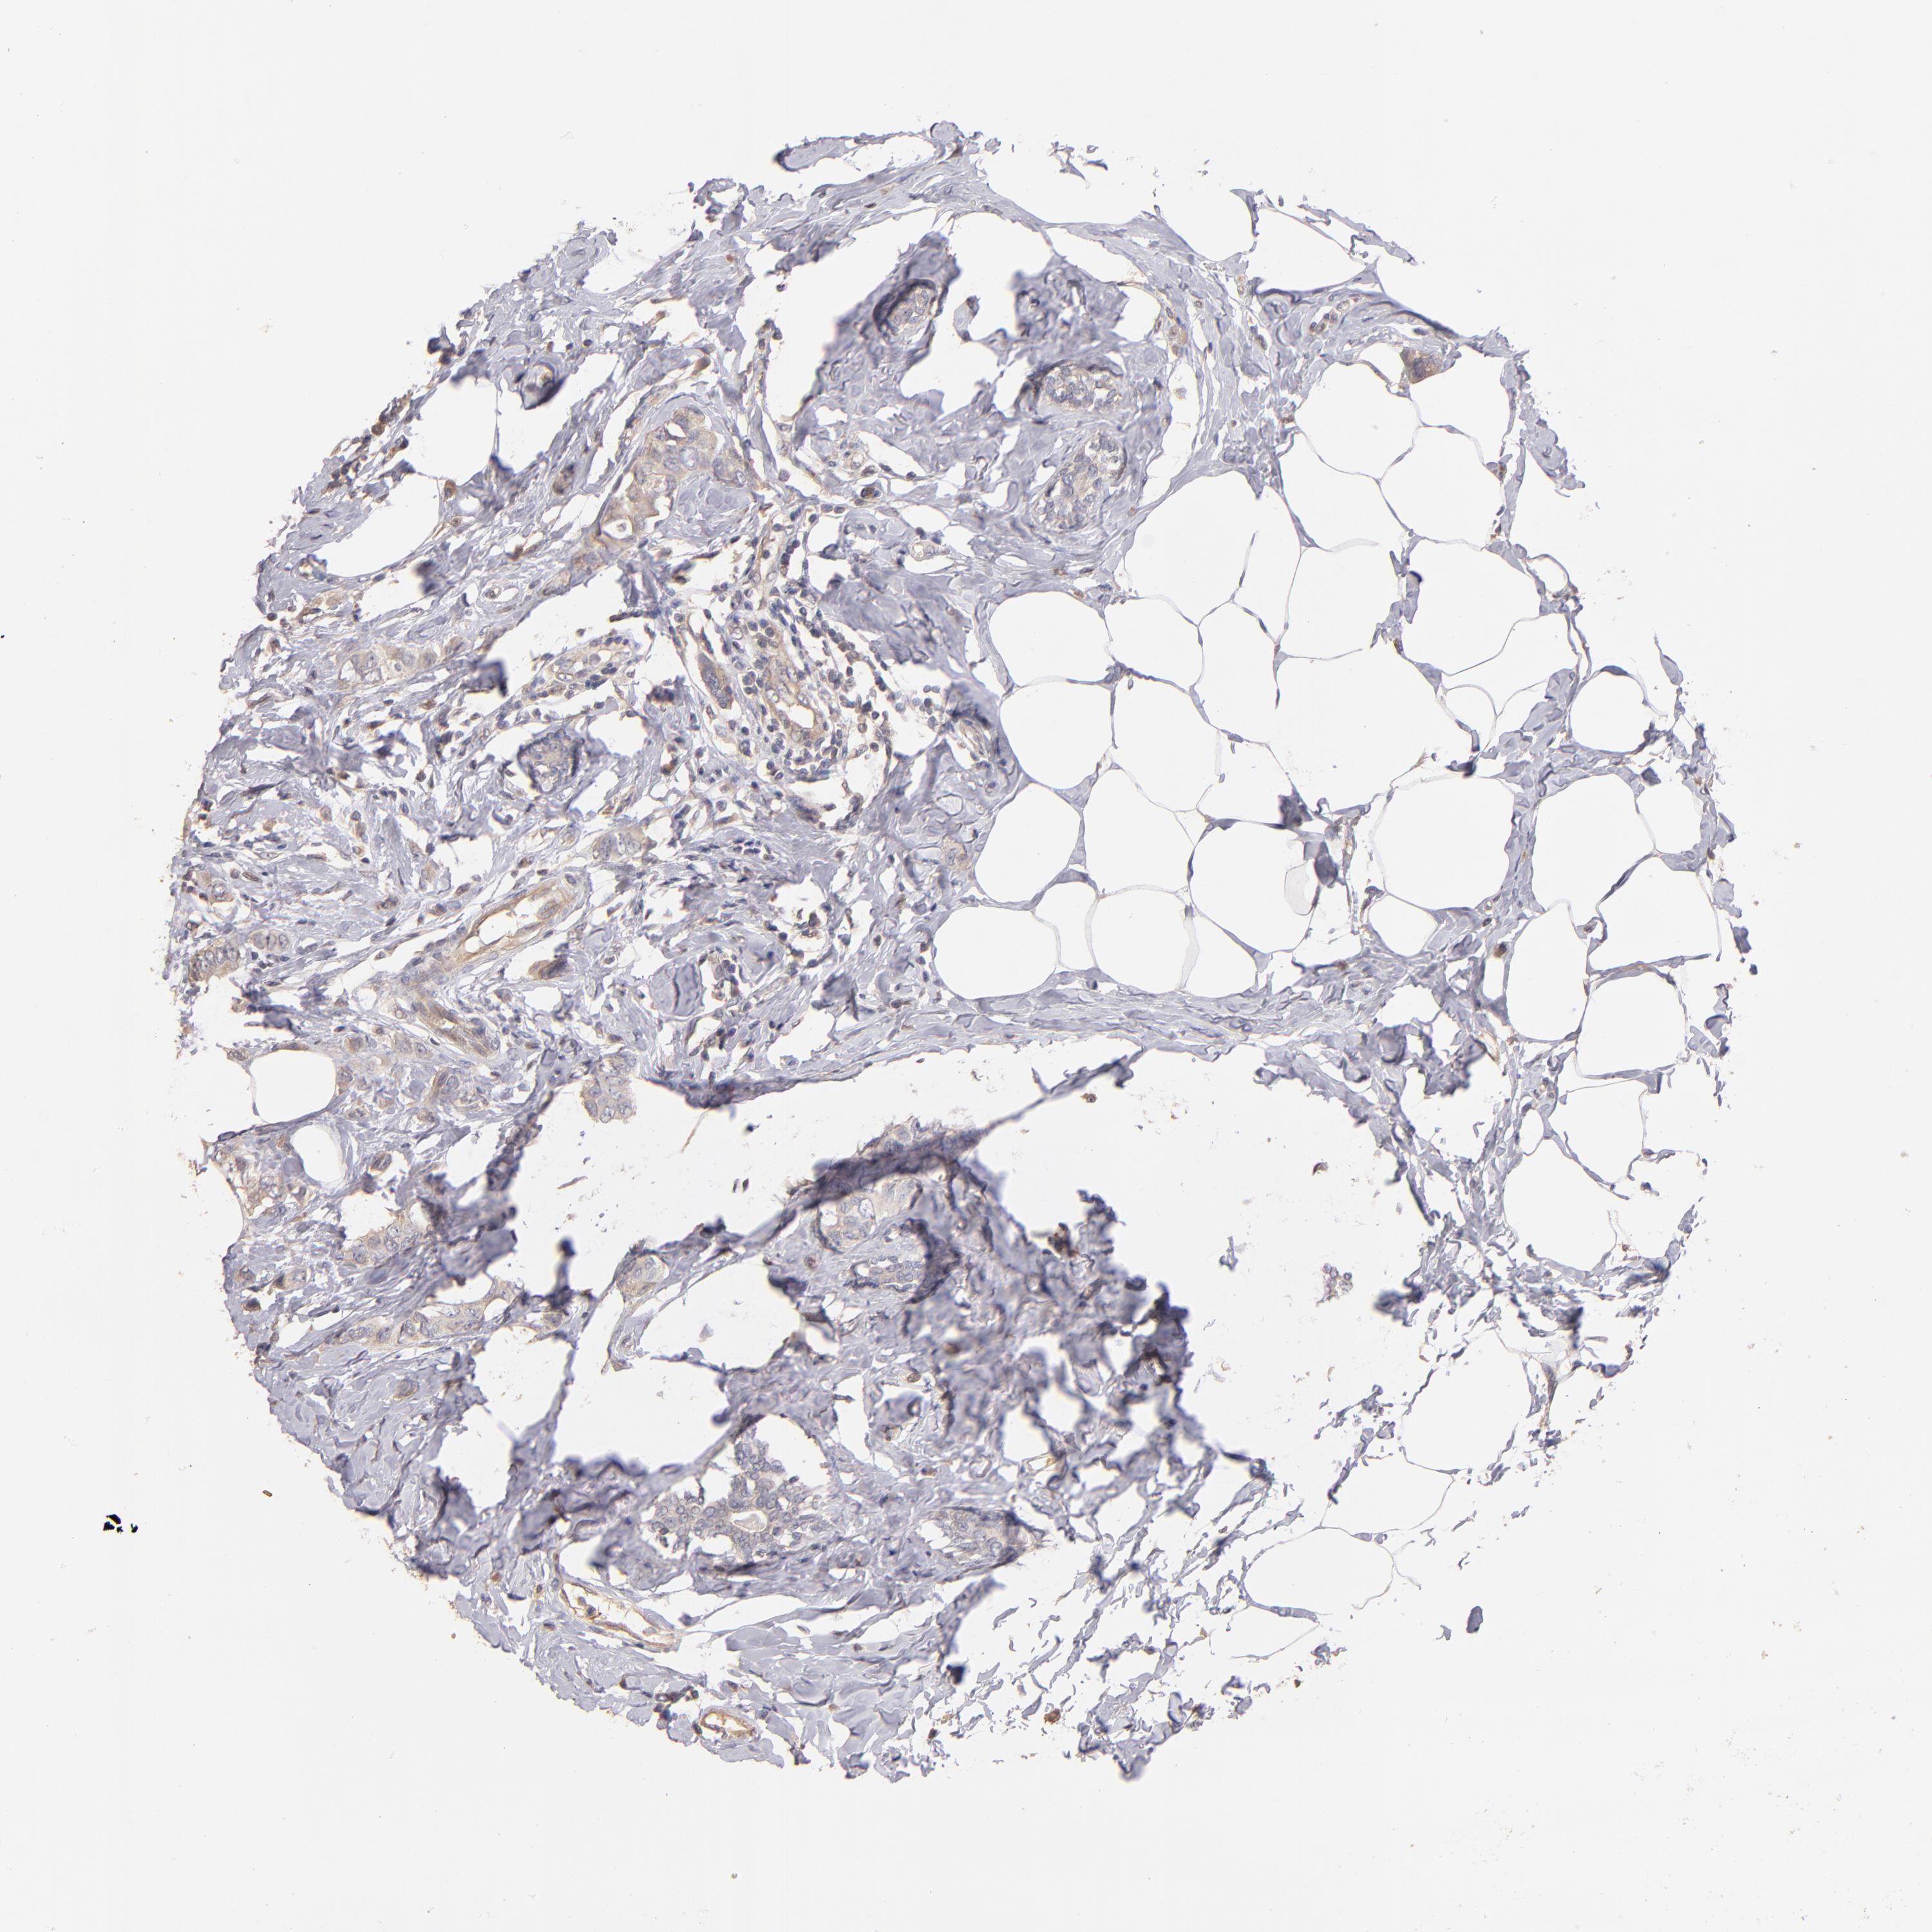

CANCER BREAST CANCER Show tissue menu

BRCA TCGA BRCA VALIDATION PROTEIN EXPRESSION

ANTIBODIES

AND

VALIDATION